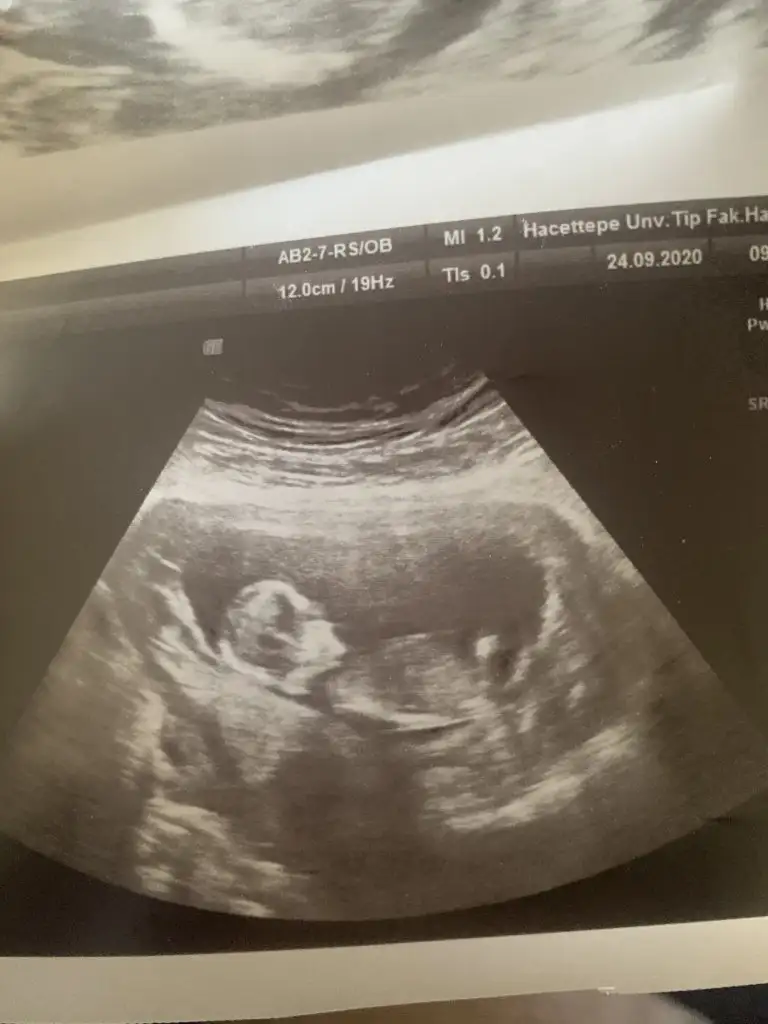

Canım 11 de büyük olasılık kız 12 de nubu kalktı kız da olabilir erkek de dedi. 15 te %100 kız dedi 16 da hala kız dediSize 12.haftada doktor, erkek mi dedi?

Sağlıkla gelsin prenses anket için çok teşekkür ederimIkra meyra En son size sormuştum kız sanki demiştiniz doğru cıktı bugün öğrendim kızımız oluyor inşallah cok teşekkür ediyorum :)))

Merhaba tahmininiz doğru çıktı doktorumuz %95 kız dediDr tam -----+ nubtan geçmiş ölçümü emin değilim sanki kız 11 12 13 haftalar olursa paylasin

Sağlıkla gelsin prensesMerhaba tahmininiz doğru çıktı doktorumuz %95 kız dedi